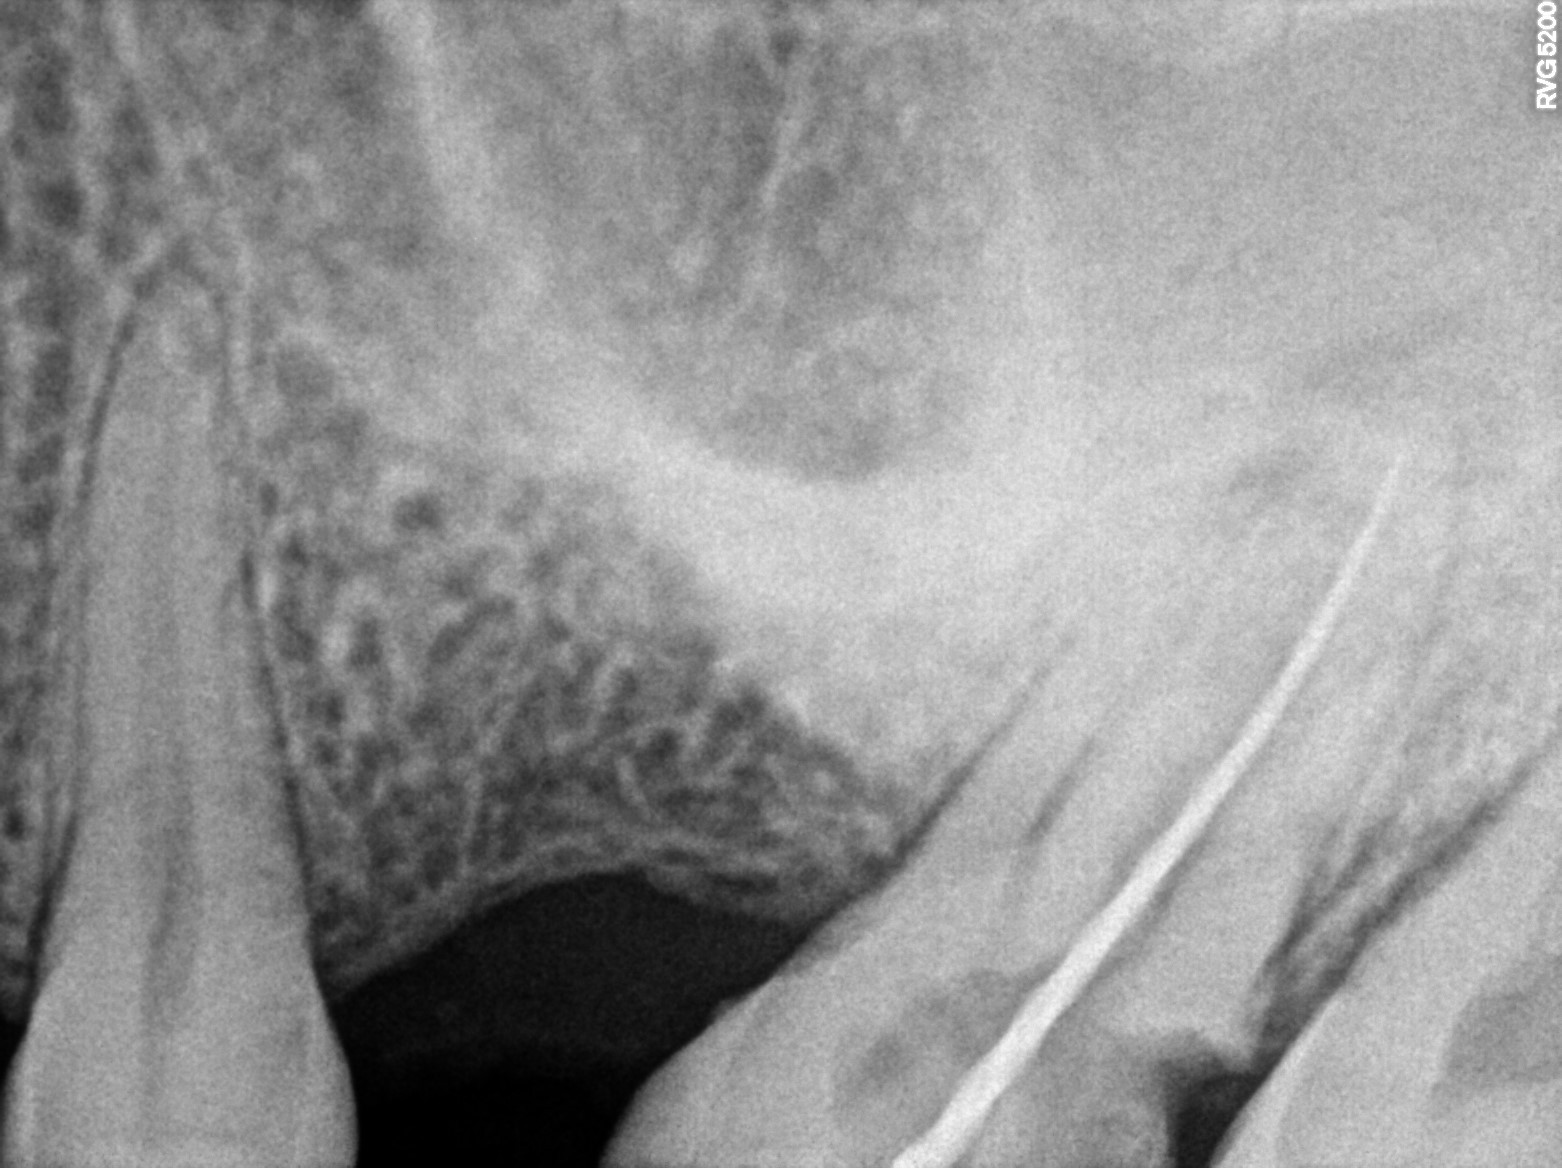

Dental Radiographs FHIR: DocumentReference · LOINC 24641-7

xray_1772815944_1.jpg

24641-7